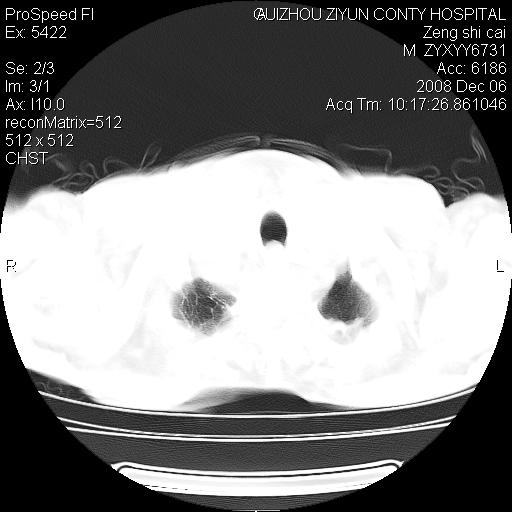

标题: CT16961:M、71岁,咳嗽半年,无血痰;胸片示右肺占位。 [打印本页]

标题: CT16961:M、71岁,咳嗽半年,无血痰;胸片示右肺占位。

1)考虑右肺上叶纵隔型肺癌伴纵隔淋巴结转移。2)心包积液,双侧胸腔积液。

右肺癌并纵隔淋巴转移,腹膜后转移可能性大,两侧胸腔积液

右肺上叶纵隔型肺癌伴纵隔淋巴结转移。心包积液,双侧胸腔积液。